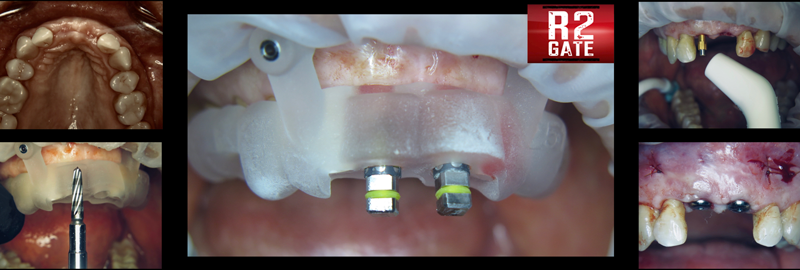

A stackable metallic guide22 (Figure 14) (Chrome GuideSmile, Chrome; alternatively: stackable non-metallic guide, Surgical Guide and Start Bit, NDX nSequence; stackable non-metallic guide, Anatomic Guide, 3Sixty) was created through the use of planning software (Blue Sky Plan®, BlueSkyBio; alternatively: R2GATE®, MegaGEN; RealGUIDE Plan, RealGUIDE). A pin installation guide that seats over the existing teeth was used to install a foundational base for which the remaining stackable guides could be attached. The attachments seat and lock by means of a Swiss locking mechanism. After PET was performed and the remaining root sections were shaped and cleaned, a scalloping guide was inserted to aid in hard tissue sculpting. This sculpting is predetermined by the heights of contour of the prefabricated provisionals incorporating desired emergence profiles. Surgical guidance of subsequent drills and implants (AnyRidge; alternatively: Neodent® Grand Morse, Straumann; NobelReplace®, Nobel Biocare) was delivered using the osteotomy guide. Multi-unit abutments were inserted to create passivity and path of insertion. Temporary cylinders were attached, and the prefabricated metal-

reinforced provisional (Figure 15) was luted in the mouth with intraoral pick-up material, creating a screw-retained provisional appliance (Fig-

Fig 14. A 3D-printed

stackable metallic surgical guide was fabricated for bone scalloping,

osteotomy preparation, implant placement, and provisional delivery.

The stackable components are attached through a Swiss locking

mechanism indicated by the blue pins.